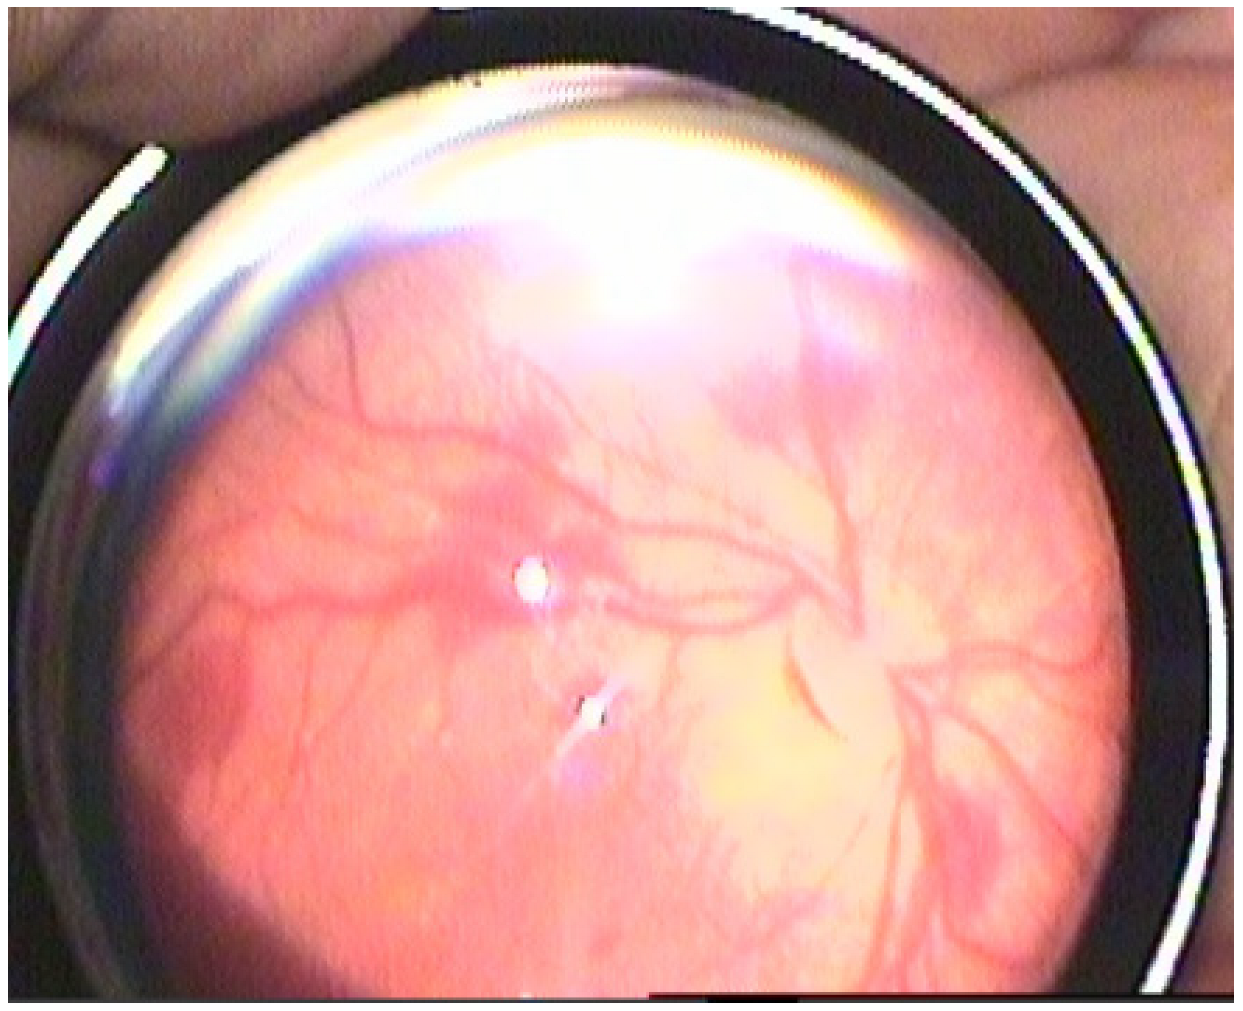

Retinal hemorrhages were identified in 178 eyes (42.3%), while RS were observed in 180 eyes (42.8%). The prevalence of both RH and RS was significantly higher in neonates with Stage 2 and Stage 3 HIE (p < 0.001). Examples of retinal hemorrhages and Roth spots are presented in Figure 1, Figure 2 and Figure 3. The mean resolution time for RH and RS was 20.21 ± 6.19 days and 13.3 ± 2.2 days, respectively. Notably, the resolution time for RH and RS was significantly prolonged in the Stage 3 HIE group compared to the other groups (p < 0.001). Moreover, an increasing HIE stage was associated with more severe RH, as classified by the Egge classification system. Detailed data regarding RH are presented in Table 2. Importantly, all instances of RH and RS were bilateral.

Figure 1. Grade 2 retinal hemorrhage.

Retinal hemorrhages were classified into three grades according to the classification proposed by Egge et al. [16]. Grade 1 RH were defined as small hemorrhages within a limited area, characterized by fine linear bleeding confined to the peripapillary region. Grade 2 RH included a slightly larger extent of hemorrhage, with patchy, flame-shaped bleeding extending over an area not exceeding the diameter of the optic disc. Grade 3 RH were characterized by hemorrhages exceeding the optic disc diameter, accompanied by flame-shaped bleeding along the retinal vasculature and macular involvement. As Roth spots are not incorporated into this classification system, they were documented separately when observed.